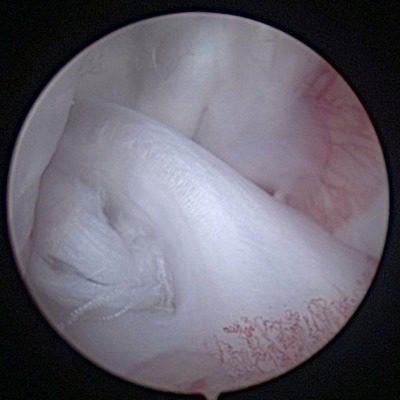

Medial Meniscus Damage